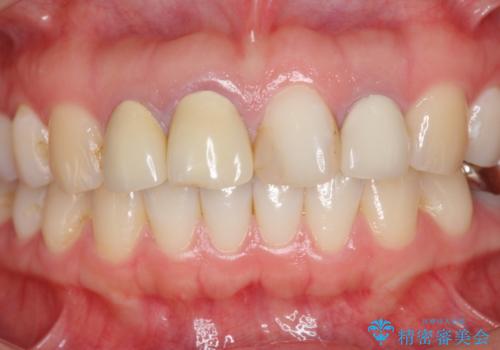

審美的なジルコニアクラウンを装着し、審美性が回復されたと満足いただくことができました。

- 37万円(仮歯×3・ファイバーコア×2・ジルコニアクラウン×3)費用は治療当時の料金となります